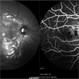

- Ocular Histoplasmosis With Macular Changes

- ocular histoplasmosis syndrome (OHS), macular changes

- Ocular histoplasmosis with macular changes.